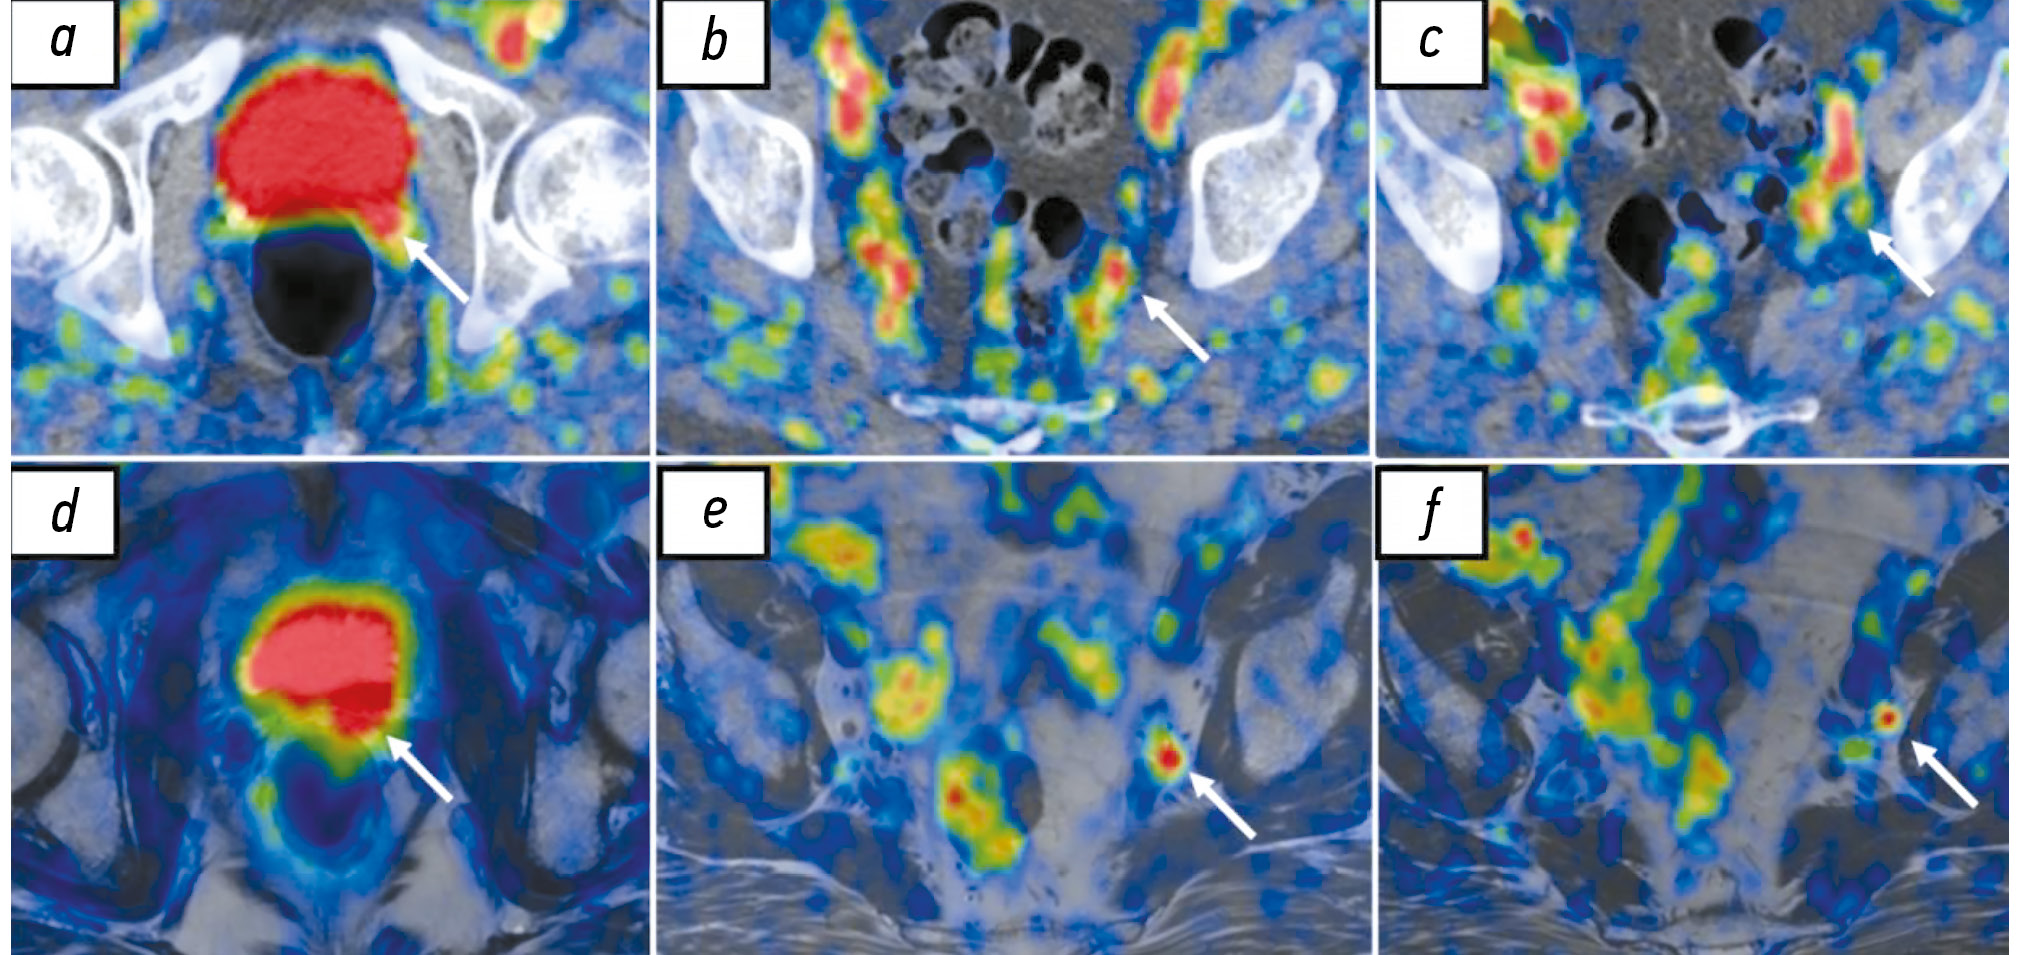

В исследовании N. Guberina и соавт. [85], опубликованном в 2020 году, 93 пациентам с биохимическим рецидивом РПЖ после радикальной простатэктомии выполнены ПЭТ/КТ и ПЭТ/МРТ с 68Ga-ПСМА-11. ПЭТ/МРТ осуществлена сразу после исследования МСКТ. Средняя концентрация ПСА в группе обследованных пациентов составил 1,64 нг/мл (0,59–4,7 нг/мл). В результате с помощью ПЭТ/МРТ диагностировано 148 из 150 очагов патологической экспрессии ПСМА, выявленных на ПЭТ/КТ (за исключением двух лимфатических узлов), и 11 дополнительных очагов (5 изменённых лимфатических узлов и 6 участков локального рецидива). При этом разница в чувствительности этих гибридных методов обусловлена различиями в чувствительности их ПЭТ-компонентов, а совсем не различиями между КТ и МРТ. Большую (98,8 против 93,2%) чувствительность метода ПЭТ/МРТ в этом исследовании возможно объяснить наличием силы Лоренца, воздействующей на позитрон в условиях магнитного поля высокой напряжённости и заставляющей его двигаться по спирали, результатом этого является уменьшение расстояния между точкой испускания позитрона и аннигиляции, что сопровождается улучшением пространственного разрешения (рис. 4) [86]. Схожие результаты получены в исследовании S. Lutje и соавт. [87], опубликованном в 2017 году, где у 25 пациентов с биохимическим рецидивом с помощью ПЭТ/МРТ с 68Ga-HBED-CC-ПСМА выявлено 14 очагов локального и 23 патологически изменённых лимфатических узла. Кроме того, ПЭТ/КТ с 68Ga-HBED-CC-ПСМА у этих же пациентов позволила обнаружить также 14 участков местного рецидива, 20 ПЭТ-позитивных лимфатических узлов, не отмечено разницы чувствительности методов в выявлении костных метастазов. В двух исследованиях выявлено, что большая чувствительность ПЭТ/МРТ с 68Ga-ПСМА-11 в сравнении с ПЭТ/КТ с аналогичным РФЛП (67,9 и 64,2% соответственно) в диагностике местного рецидива по данным анализа исследований 53 пациентов с биохимическим рецидивом РПЖ обусловлена вкладом МРТ-компонента за счёт более чёткой детализации структур малого таза, что позволило выявить опухолевую ткань на фоне артефактов от мочевого пузыря [83, 88].

Рис. 4. Результаты совмещённой позитронно-эмиссионной и компьютерной томографии с 68Ga-простатоспецифичным мембранным антигеном (a, b, c) и совмещённой позитронно-эмиссионной и магнитно-резонансной томографии с 18F-простатоспецифичным мембранным антигеном-1007 (d, e, f) пациента с рецидивом рака предстательной железы после радикальной простатэктомии, собственное наблюдение: a, d — локальный рецидив в области везикоуретрального анастомоза слева (стрелки); b, c — повышенная экспрессия простатоспецифичного мембранного антигена в неувеличенном левом внутреннем подвздошном лимфатическом узле; c — отсутствие визуализации повышения экспрессии простатоспецифичного мембранного антигена (стрелка); f — визуализация повышения экспрессии простатоспецифичного мембранного антигена (стрелка).